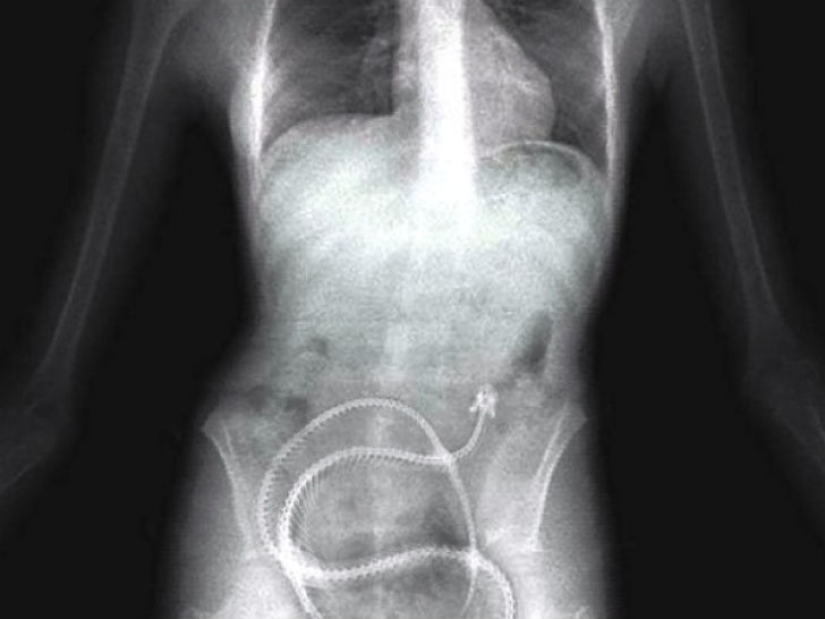

Algunos presos están dispuestos a tragar cualquier cosa para salir de la cárcel, por ejemplo, al hospital, incluso los resortes del colchón.